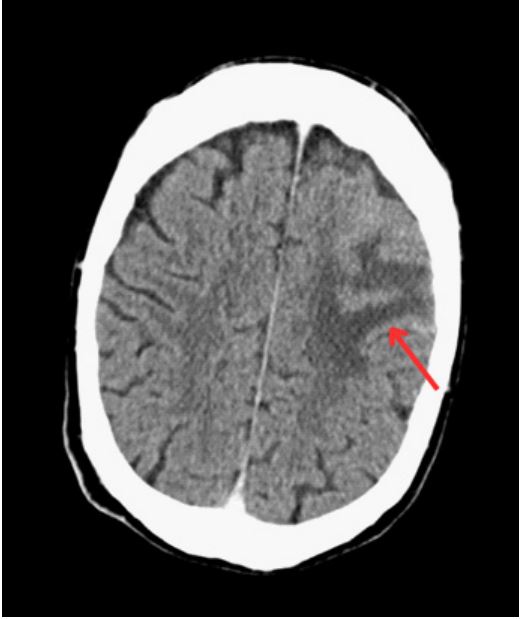

He commenced on Dexamethasone 8mg orally (PO) and Keppra 250mg. A subsequent magnetic resonance imaging (MRI) of the brain demonstrated vasogenic oedema and abnormal leptomeningeal enhancement in left frontal lobe with evidence of subarachnoid blood (Figure 2).

Figure 2: (A) MRI brain demonstrated vasogenic oedema and abnormal leptomeningeal enhancement in left frontal lobe with evidence of subarachnoid blood; (B) MRI brain one week later demonstrated ongoing vasogenic oedema, with interval decrease in leptomeningeal enhancement and stable leptomeningeal hemosiderin deposits, with no frank subarachnoid haemorrhage; (C) MRI brain on treatment demonstrating resolution of leptomeningeal thickening and vasogenic edema.

Clinically, the patient remained stable, with some improvement with time. A lumbar puncture was performed which provided clear cerebrospinal fluid with no leukocytes detected. The MRI brain was repeated a week later, which demonstrated ongoing vasogenic oedema, with interval decrease in leptomeningeal enhancement and stable leptomeningeal hemosiderin deposits, with no frank SAH.

At this time, it was felt that there was limited premise in support of an infective, neoplastic, or traumatic cause for these symptoms, making an inflammatory cause the most likely etiology. Thereafter, rheumatology and otolaryngology consultations were sought, and subsequent vasculitis screen elicited a positive p-ANCA and an elevated proteinase-3 (PR-3) of 105 relative units/ml. On closer questioning the patient admitted to a 3-month history of dry crusting of his nose. He commenced on methylprednisolone IV for three days, before being commenced on prednisolone 60 mg PO initially (reducing slowly). The patient was then commenced on low dose oral Methotrexate (20 mg PO weekly) and IV Cyclophosphamide (Bermingham protocol). The MRI brain was repeated 1 month after treatment, which demonstrated the complete resolution of leptomeningeal thickening and a small focus of vasogenic edema (Figure 4), with a focal defect in the nasal septum, supporting a formal diagnosis of cerebral vasculitis secondary to GPA. At follow up review in clinic at 3 months the patient’s signs and symptoms had completely resolved. He remains well on Prednisolone 10 mg PO daily and Methotrexate 20 mg PO weekly.